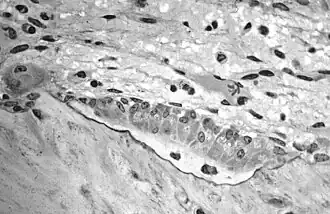

Osteoblasts actively synthesizing osteoid containing two osteocytes.

Osteoblasts actively synthesizing osteoid containing two osteocytes..jpg) Illustration showing bone remodelling cycle